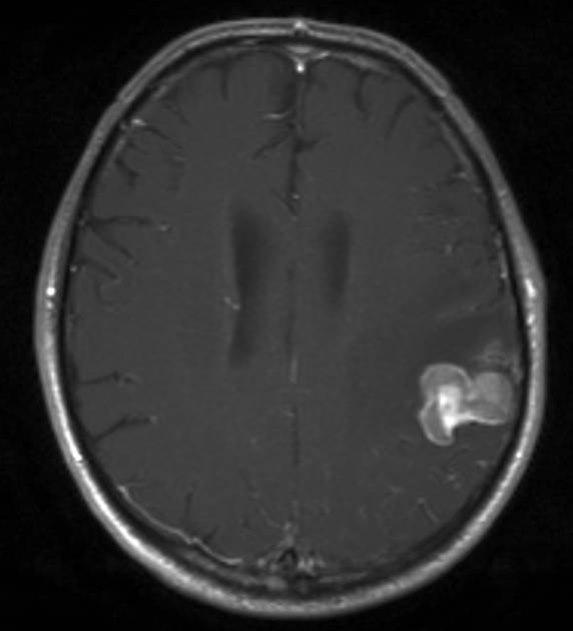

MR er den mest sensitive undersøkelsen såvel til påvisning av små metastaser som til å påvise andre sykdommer i hjernen. Ved CT av hjernen med kontrast finnes multiple hjernemetastaser hos ca. 50 prosent, ved MR-scanning hos ca. 75 prosent.